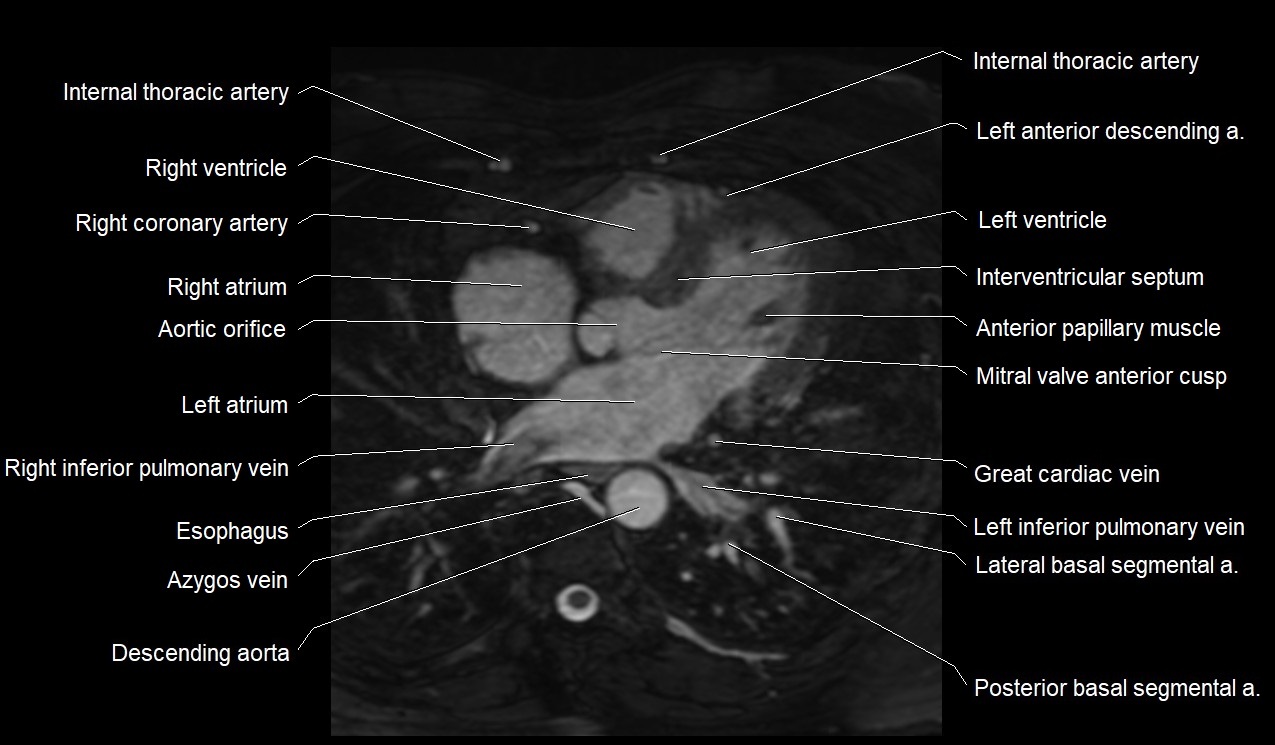

MRI image